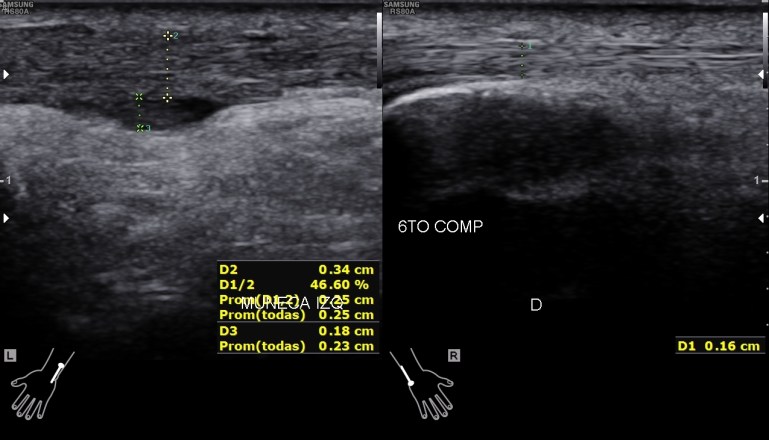

Situada en la corredera bicipital, vas a ver el bíceps como una estructura hiperecogénica, redondeada situado en el valle de la corredera. Observa como la imagen superior indica ausencia de líquido y normalidad y la inferior relación entre la anatomía y la patología donde el líquido rodea el tendón en relación con una posible tenosinovitis.